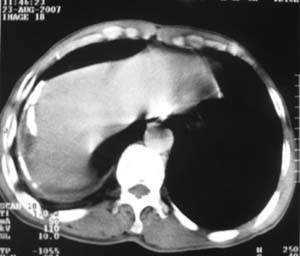

标题: CT9556:男,54岁,包裹性积液,请各位老师会诊其原因! [打印本页]

标题: CT9556:男,54岁,包裹性积液,请各位老师会诊其原因!

男,54岁,无任何不是感.体检发现右肺部阴影.现行ct进一步确诊.

包裹性积液伴胸膜钙化

右侧胸廓塌陷,肋间隙变窄,肋骨增生变粗,脏壁层胸膜肥厚、钙化。符合陈旧性结核性脓胸改变

右侧包裹性积液伴胸膜钙化.

结核性胸膜炎可能性大!脓胸!

包裹性积液伴胸膜钙化,结核性?

包裹性积液伴胸膜钙化,考虑结核性

右侧包裹性积液并胸膜钙化,性质还是结合穿刺细胞学检查的好,结核性、化脓性均会有钙化。

右侧胸膜肥厚、粘连、钙化。

右测包裹性积液并胸膜钙化,结核性脓胸还是胸膜肿瘤转移,还需要穿刺抽液

包裹性积液伴胸膜钙化,原因多种,国民一般为结核性居多